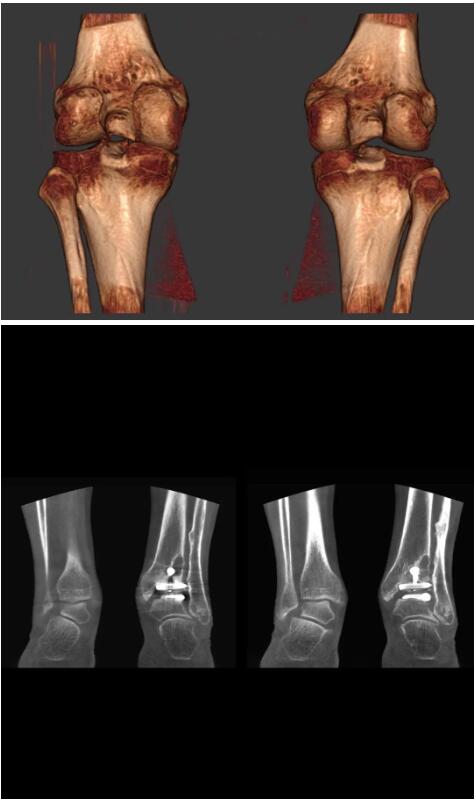

另外一款被稱為世界上最小的CT,它的重量?jī)H300磅,不僅能夠掃查足部,還可以檢查膝蓋和上肢等。

與上面介紹的CT一樣,它同樣具有輻射低、占地空間小(23*36)的特點(diǎn),隨開隨用(支持直接接入墻上的插座)。

這款CT使用非常方便,通過上下移動(dòng)保持與患者的手臂或者雙腿齊平,掃描快速,僅需要30秒左右就可以完成掃查。

以上介紹的CT均來自國(guó)外同一家公司,這些CT均配置了可視化軟件,可以進(jìn)行切片、3D重建以及大型CT附帶的所有典型的操作功能。

以下是這些“特立獨(dú)行”的CT所拍出來的圖像: